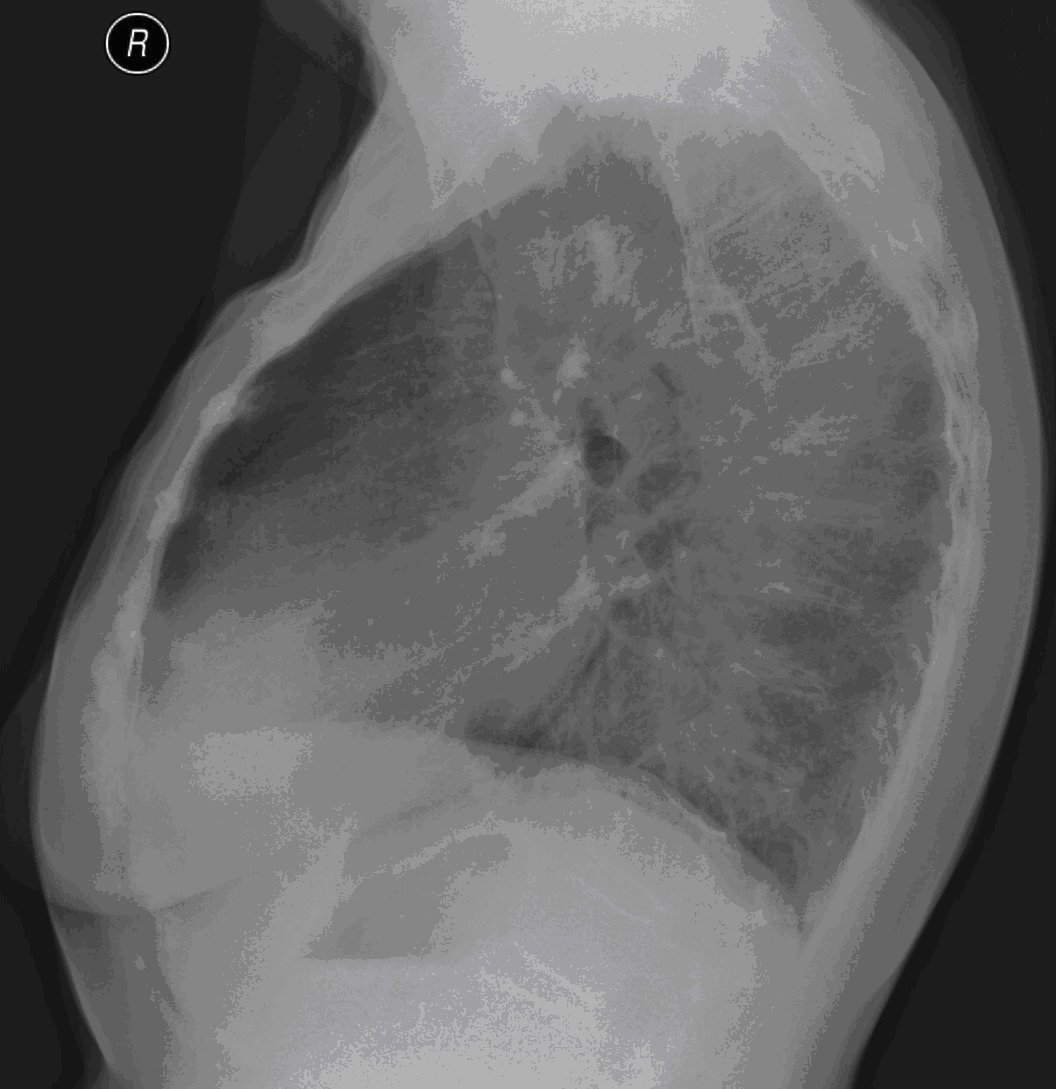

19. Tuberculosis, bidirectional chest radiographs and HRCT. (coronal reconstruction)

75 year old man: hx of hypertension, smoking. Symptoms: dyspnea, productive cough. Moist rales of auscultatory findings above the LLL, tension irritability in the level of lower dorsal spine.

a.) Chest radiograph, bilateral: Mild increased vascular markings. Extensive patchy lobar infiltration in the RUL Previous TB specific lesions in the left apex. The diaphragm contour is blurry on the right side (appr. 4 finger-wide pleural effusion). Cardiomegaly. Medium large dilated sclerotic aorta.

b.) HRCT: Reticular pattern of 10x10x5 cm area in the right apex (1st segment), (septal thickenings), mosaic-like ground glass opacity in the righ apex. Subpleural total atelectasis (mainly 1st segment): irregular mainly nodular soft tissue streak associated with the pleura (max. appr. 1 cm thickness). Some tiny subpleural emphysematous bullae in the right apex.